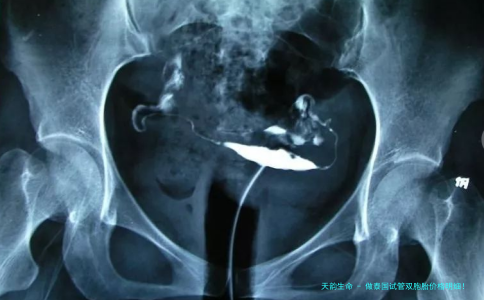

4. 卵泡取出手术费用

卵泡取脱手术是试管婴儿过程当中极为重要的一步。手术平常在浑身麻木下进行,保证病患在全过程中不会感触酸麻。卵泡取动手术的费用大致在2000-3000美圆之间,详细费用取决于于手术的繁复程度和医院的器械水平。